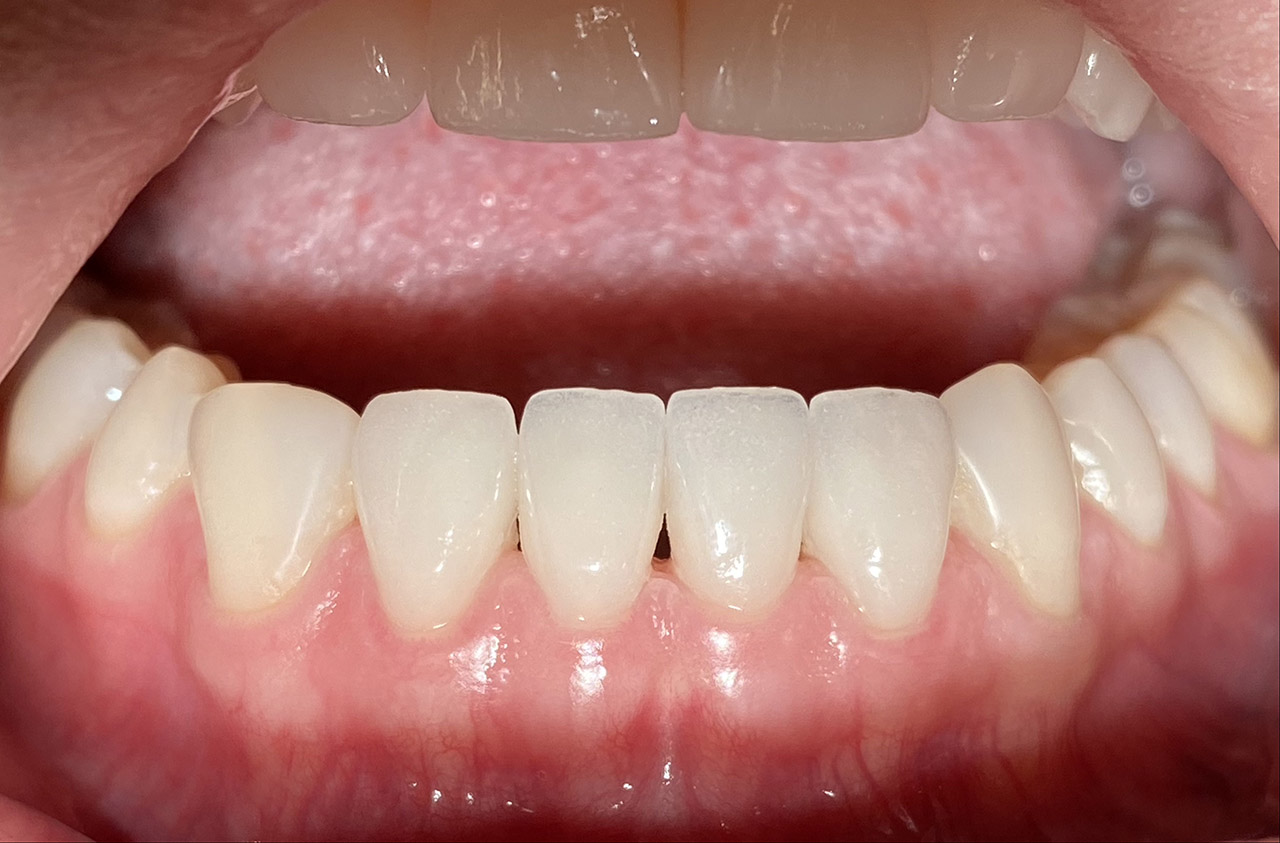

Aplasien/Nichtanlagen, dadurch bleibende Milchzähne, Diasteme/Zahnlücken,

Bleaching/Bleichen, Positionierung der Zähne/Kieferorthopädie (Dr. Maija Eltz), Verblendung mit Veneers/Keramikschalen.

Klebebrücken bei Zahnaplasie (Nichtanlage):

Vorbehandlung (Dr. Ernst Köle): Kieferorthopädischer ”Platzhalter mit provisorischem Zahn”.

Minimalinvasive Therapie: 2 keramikverblendete Klebebrücken (“Zirkonflügerl") adhäsiv zementiert.

Konservativ ohne Knochenaufbau und Schleimhauttransplantat.